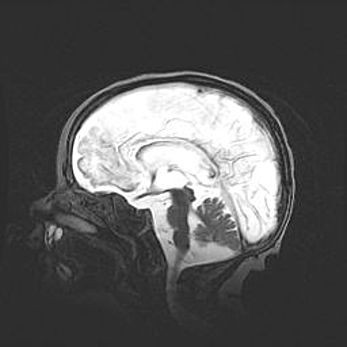

Мальформация Денди-Уокера. Киста задней черепной ямки.

Агенезия мозолистого тела.

Возраст: 2,5 месяца

Вес: 2420 г

Пол: женский

Окружность головы: 37 см

Срок гестации: 32 недели

Мальформация Денди—Уокера — редкий вид патологии ЦНС, представляющий собой врожденный порок развития каудального отдела ствола и червя мозжечка, ведущий к неполному раскрытию срединной (Мажанди) и латеральных (Лушка) апертур IV желудочка мозга. Для этогно синдрома характерна триада симптомов: гипотрофия червя мозжечка и/или полушарий мозжечка, кисты задней черепной ямки, гидроцефалия различной степени. В 70% случаев порок сочетается и с другими аномалиями головного мозга, в частности с агенезией мозолистого тела.